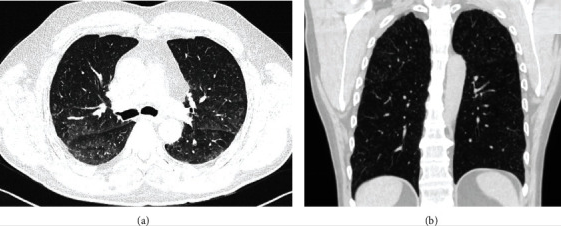

一名60岁的吸烟男子,因常规体检发现胸部X光异常而前往呼吸科进行检查。患者的既往病史包括颈动脉疾病伴中风、动脉高血压、肾结石和尿石症。没有任何已知的恶性肿瘤。患者的体格检查在正常范围内。入院时胸部高分辨率计算机断层扫描(HRCT)显示双肺实质中弥漫性、多发性、1-5mm 的结节性病变,上肺叶略占优势(图1)。

图1.高分辨率计算机断层扫描(HRCT)图像。a,b显示双肺实质中弥漫性多发结节性病变